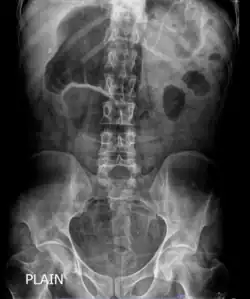

| X-ray showing distended stomach and bowel loops. Dilated bowel loops are a characteristic of chronic intestinal pseudo-obstruction. | |

In order to look into possible intestinal obstruction, radiologic examinations are essential. Simple and cheap to perform, plain film x-rays can show the traditional indicator of air-fluid levels and dilated bowel loops, which is best seen in the erect film.[25] Abdominal x-rays, however, are unable to definitively differentiate between genuine mechanical intestinal obstruction and pseudo-obstruction.[26] Afterwards, additional information is obtained by abdominal computed tomography (CT) imaging in order to rule out an extraluminal, gut wall, or intraluminal mechanically obstructive lesion.[25]